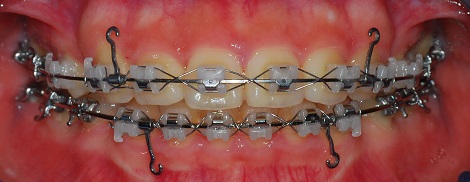

상악 사진

상악과 하악의 발치 공간의 차이가 좀 보이네요